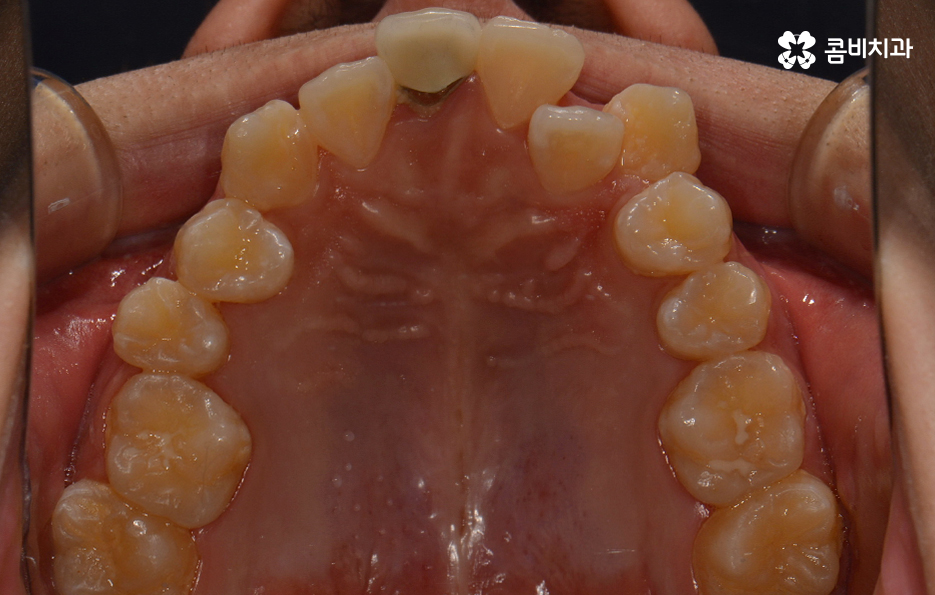

왼쪽이 윗니이고 오른쪽이 아랫니인데 치열의 불규칙함이

심한 편이다 보니 평소 음식물이나 치석이 끼기 쉬운 환경이

되고 이러한 구강 환경이 지속된다면 충치와 잇몸질환의 발생률이 높아질 수 있어요.

덧니는 치아가 제대로 자리를 잡지 못하여 발생하게

되는 경우라고 할 수 있는데 턱이 작거나 치아가 큰 경우 치아가

정상적으로 나올 공간이 부족하여 생기는 경우가 일반적이라고 할 수 있어요.